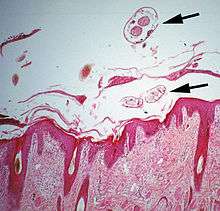

- Psoroptic mites feed superficially at the stratum corneum. The photograph of a histological section of skin infested with Psoroptes ovis, and the photograph of the surface of a host's skin infested with P. ovis looking like white dots, show this type of feeding.

The clinical manifestation of infestation with psoroptic mites is usually called mange and sometimes scabies, but the skin disease of sheep caused by Psoroptes ovis is often known locally as sheep scab. This species may affect its hosts severely enough to reduce their gain in weight.[25] Costs to farmers of controlling sheep-scab in Britain were at £8 million (US$12 million) annually in 2005.[26] Transmission between hosts is readily accomplished by contagion during flocking contact and also on fomites such as scraps of sheep's wool because these relatively large and robust mites can survive for one to two weeks off their host. Psoroptes ovis infests the superficial layers of the skin. Irritation of the outer skin by the mite's mouthparts and saliva results in a complex form of cutaneous hypersensitivity and inflammatory exudation of serum and fresh cells. The mites feed on this moist exudate.[27] The skin loses its hair (depilation) at the sites of infestation and this may be extensive. As a result of the movement of the mites into areas of fresh skin, large scabs accumulate on the raw skin left behind. The mites cause intense pruritus (itching). In cases of heavy infestations, the host grooms compulsively, aggravating the depilation, and it may become mentally distressed.[28] Psoroptes ovis infests sheep worldwide and can be a serious welfare and animal-production problem for sheep farmers. Infestations of cattle with mites of the similar genus Chorioptes, in combination with Sarcoptes mite infestation, has been shown to cause a failure to gain body weight by 15.5 kg to 37.2 kg over a two-month period compared to cattle without the mites.[29]